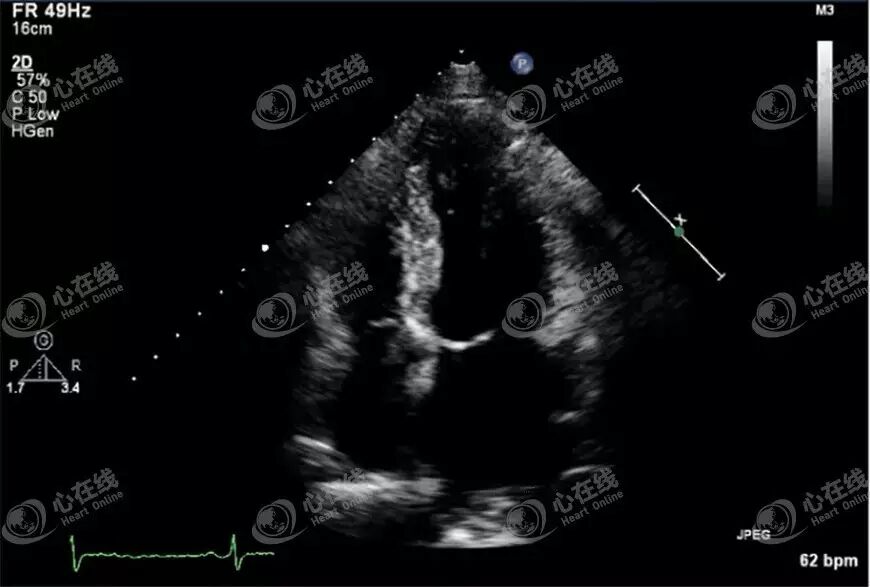

(3)假性室壁瘤

图A显示右室的十字形占位性病变,观察可见右室房室环部位出现肿块,且右心明显扩大。观察图B可见左室外侧有一个瘤腔,且左室壁连续中断,彩色多普勒可见贯通于左室腔和瘤体之间的血流信号,提示假性室壁瘤。

对心尖室壁瘤形成的患者经介入方法置入“降落伞”(图B),可改善心功能。图A、C为置入“降落伞”术后的超声动态图。